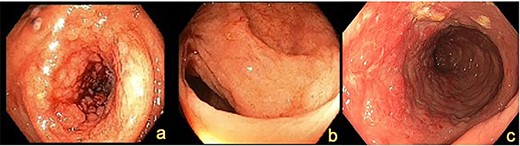

Histopathology confirmed metastatic ILC with immunohistochemistry (IHC) positive for CK7, GATA3, GCDFP-15 and ER but negative for PR and HER2 (Fig. 3a and b). Postoperative mammogram and ultrasound showed no obvious breast lesion, but suspicious left axillary lymphadenopathy. Following her recovery, the patient received adjuvant endocrine and targeted biological treatment in the form of letrozole and Palbociclib, respectively.

IHC staining showing (a) Gata3 positive cells, (b) ER positive cells and (c) macroscopic hemicolectomy specimen with diffuse infiltrative ILC.

The patient underwent an extended right hemicolectomy (Fig. 3c). Histopathology confirmed diffuse infiltration by metastatic ILC with multifocal lymphatic and perineural invasion. The tumor was strongly HER2 positive, weakly ER positive (10%) and PR negative. The patient proceeded to palliative paclitaxel chemotherapy. Unfortunately, the patient had rapid disease progression and was eventually transitioned to comfort care measures.